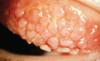

Quais as característica clínicas da conjuntivite papilar gigante?

Aumento da mobilidade e intolerância às Lentes de Contato

Papilas gigantes > 3mm, predominando na pálpebra superior

A córnea raramente é acometida